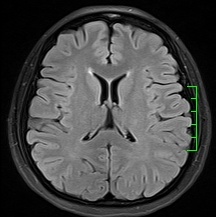

磁共振——锁定“水”的科技

磁共振(MRI)与普通X线、CT不同,不依赖于X线成像,而是氢原子核,也可以理解为水。以前称为核磁共振,是因为MRI的原理是用较大的磁场,使人体内原本随意排列的氢原子核磁场的磁力线方向统一,再突然把磁场的作用去掉,监测其中信号的变化。MRI成像依靠不同组织含氢核数目不同,或者可以近似理解为不同组织含水量不同,形成图像差异,来区别组织。所以MRI对中枢神经系统和软组织有着良好的分辨能力,适用于软组织、神经系统疾病、内脏器官,并且多序列及多参数成像、功能成像。不过,MRI检查时间较长,价格较贵,预约时间较长。

磁共振平扫图像